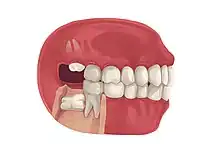

Impacted third molar

Impacted wisdom tooth